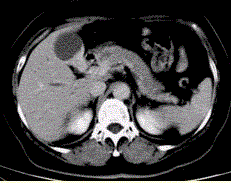

患者女,50岁,右上腹痛,向肩胛部放射,伴有消瘦、乏力。查体:皮肤巩膜黄染,墨菲(Murphy)征阳性。CT示胆囊壁不规则增厚(下图)。该病CT增...

问题 患者女,50岁,右上腹痛,向肩胛部放射,伴有消瘦、乏力。查体:皮肤巩膜黄染,墨菲(Murphy)征阳性。CT示胆囊壁不规则增厚(下图)。 该病CT增强检查的表现为

选项 A.持续明显强化趋势 B.斑片状强化 C.呈“快进快出” D.延时期强化 E.未见明显强化

答案 A